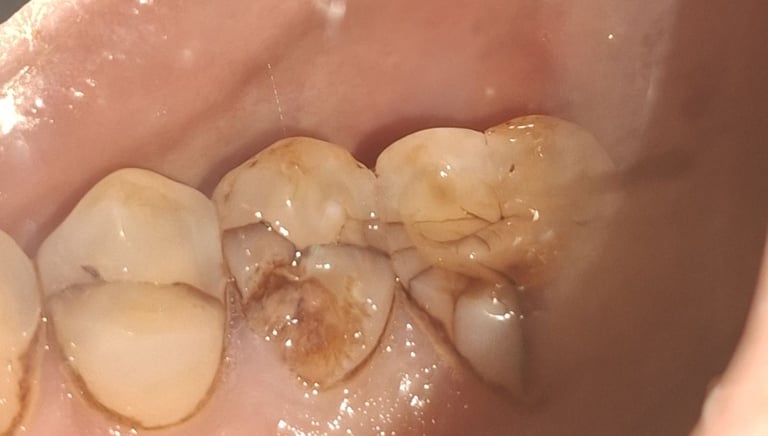

Clinical pictures of teeth requiring RCT

All images are of real cases of teeth where Root canal treatment was performed to remove infection and preserve the natural tooth restoring normal chewing and function of teeth.